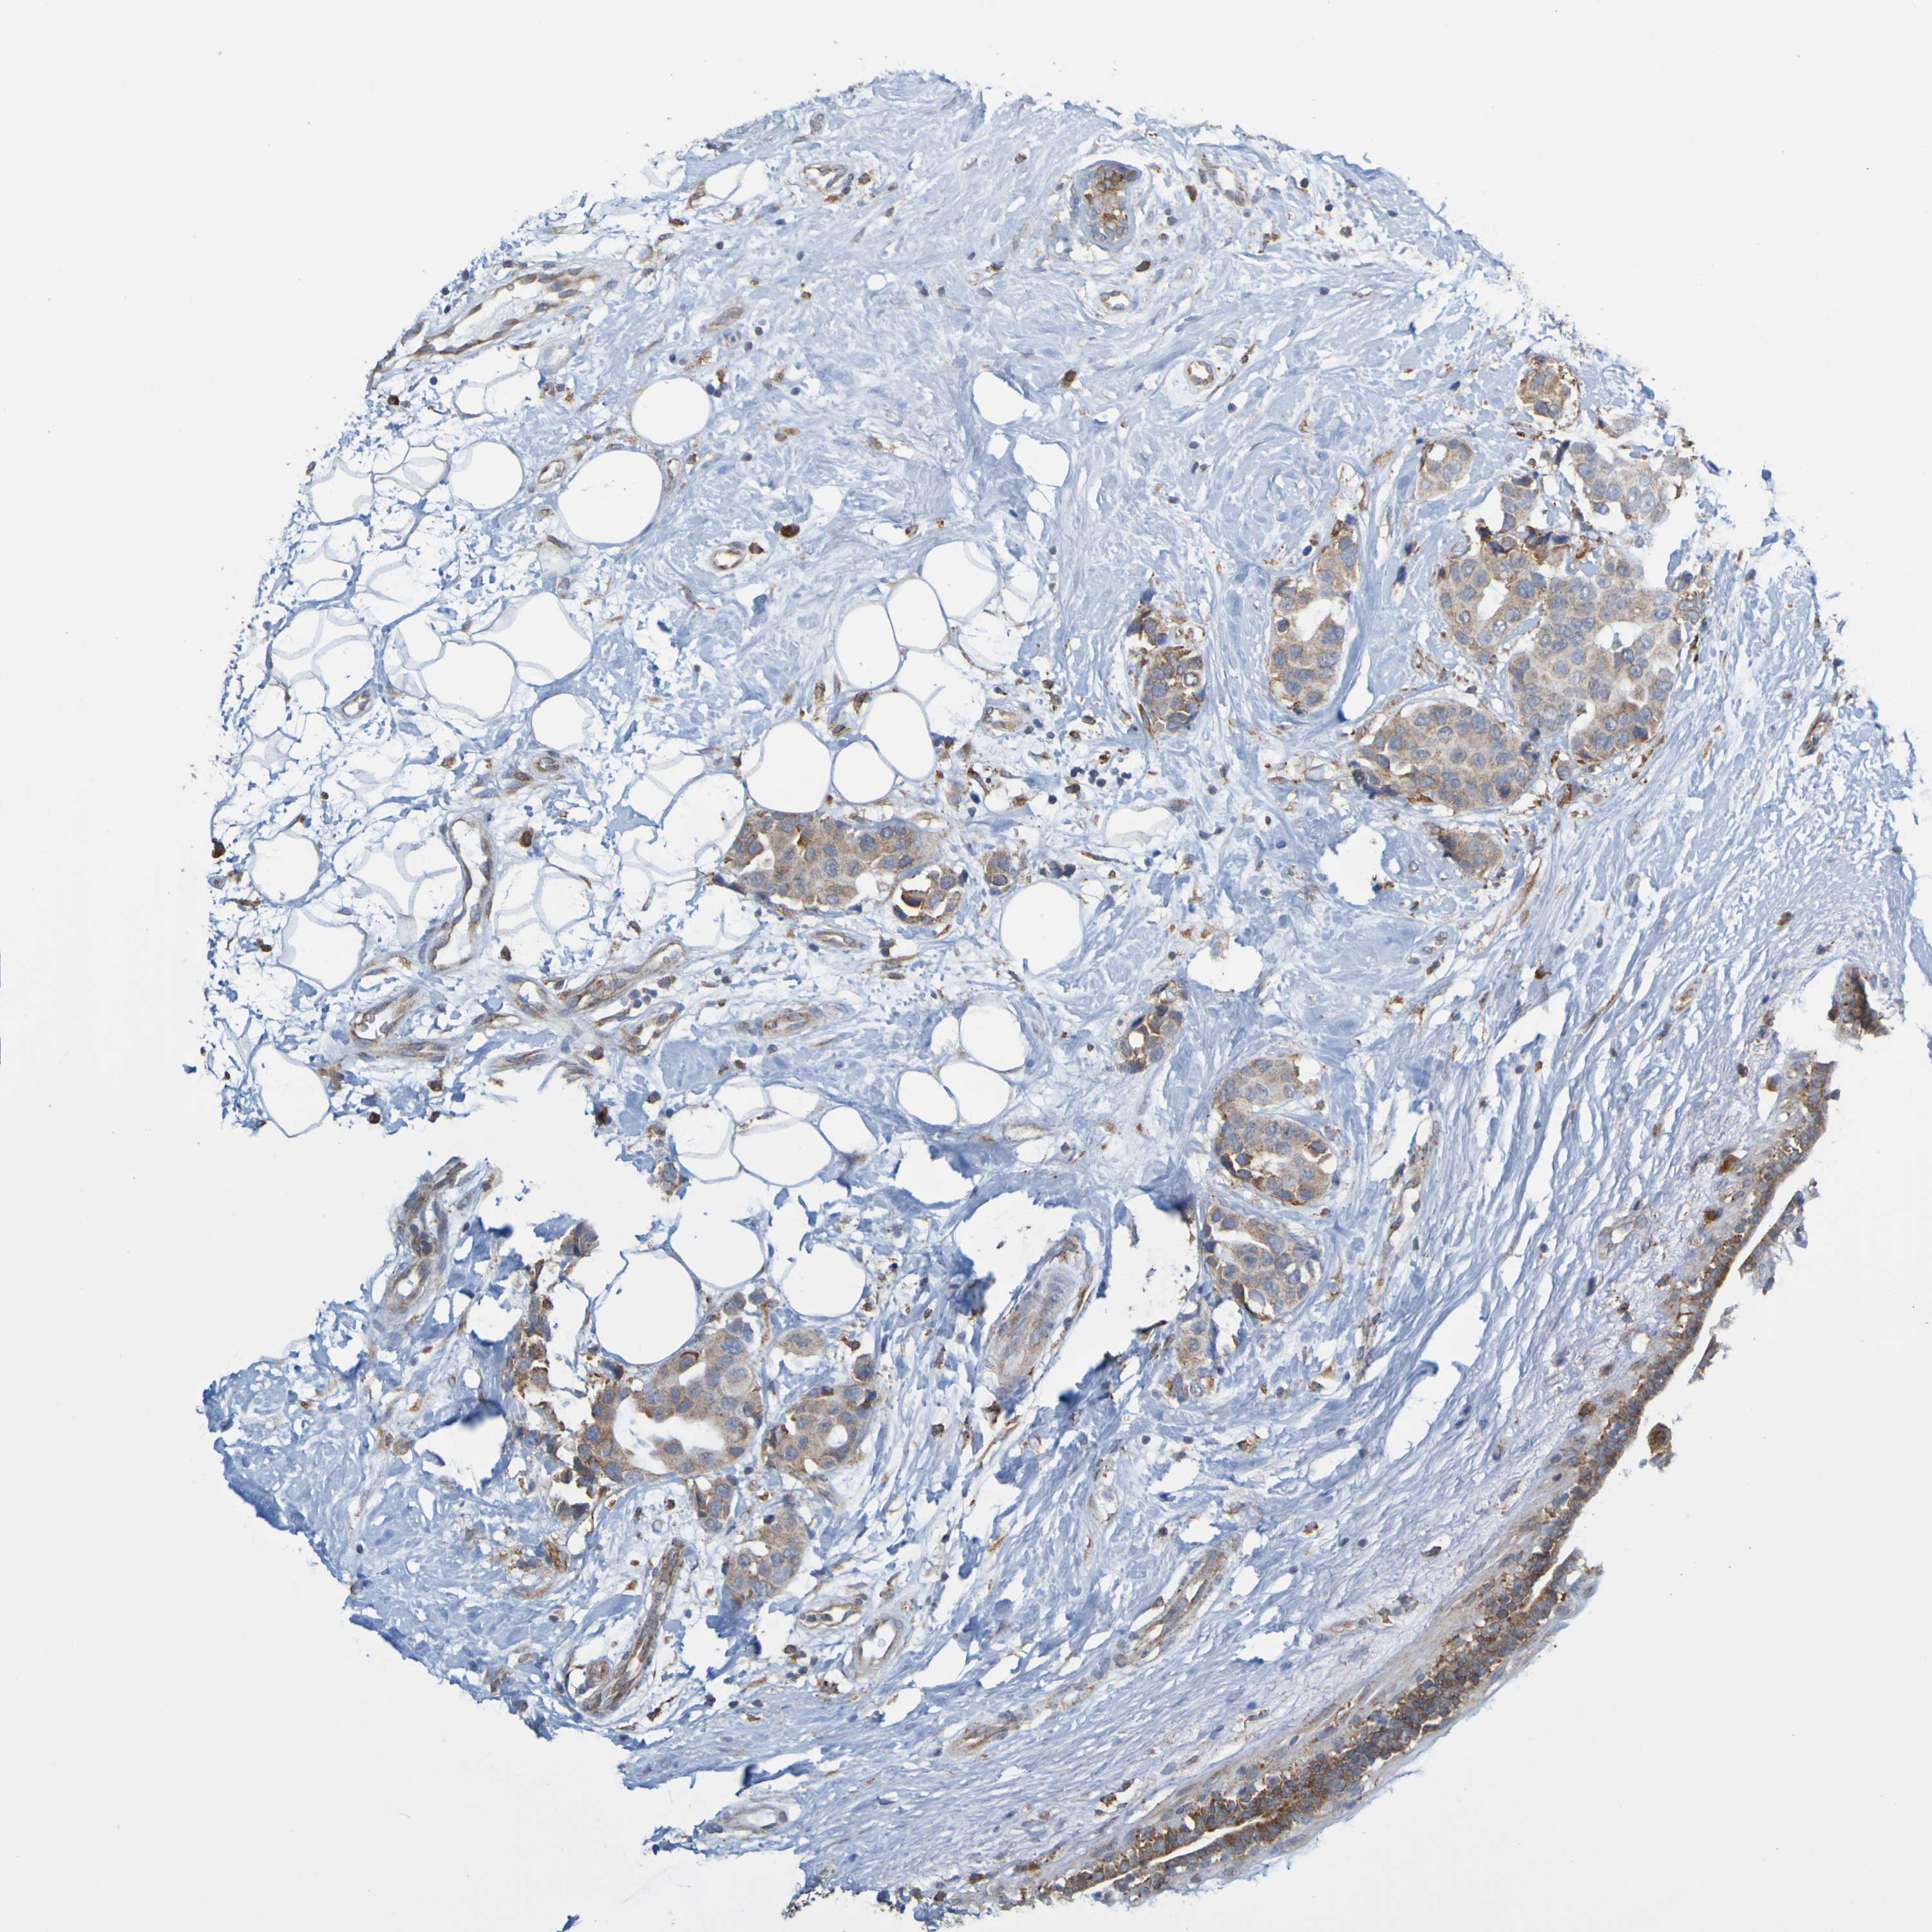

CANCER BREAST CANCER Show tissue menu

BRCA TCGA BRCA VALIDATION PROTEIN EXPRESSION